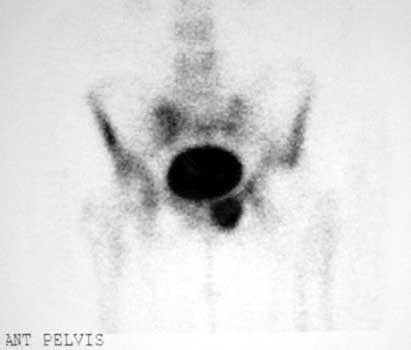

Fractures

Most frequently occur near distal stem of femoral component

Osteopenia due to long periods of inactivity secondary to pain and disability predispose to insufficiency fractures after surgery when patients are ambulating more frequently.

STRESS OR INSUFFICIENCY

Left pubic bone

Left inferior pubic ramus